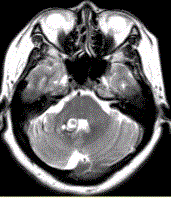

问题 患者女,41岁。头痛半年,加重10d。头部MRI显示如下图。 关于发育性静脉畸形的描述正确的是

选项 A.MR增强检查显示“海蛇头”样表现 B.常发生于侧脑室额角白质或Ⅳ脑室周围白质 C.扩张的髓静脉呈伞样汇集,经粗大的静脉引流入静脉窦或深部室管膜静脉 D.病变较小,T1WI可正常,T2WI可见血管流空 E.影像学首选MRT1C+MRV F.T2*WI可显示出血及伴有其他血管畸形 G.15%~20%伴有海绵状血管瘤